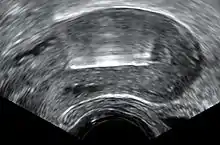

Inmediatamente antes de la inserción, el clínico realizará un examen pélvico para determinar la posición del útero.[22] Tras el examen pélvico, se mantiene abierta la vagina con un espéculo.[38] Se utiliza un tenáculo para estabilizar el cuello uterino y el útero.[38] Se puede utilizar un sonda uterina para medir la longitud y la dirección del canal cervical y el útero con el fin de disminuir el riesgo de perforación uterina. El DIU se coloca utilizando un tubo estrecho, que se introduce a través del cuello uterino hasta el útero. Unos hilos cortos de monofilamento de plástico/nylon cuelgan del útero hacia la vagina. El clínico recortará los hilos para que sólo sobresalgan 3 o 4 cm del cuello uterino y permanezcan en la parte superior de la vagina. Los hilos permiten a la paciente o al clínico comprobar periódicamente que el DIU sigue en su sitio y facilitan la extracción del dispositivo.[22]